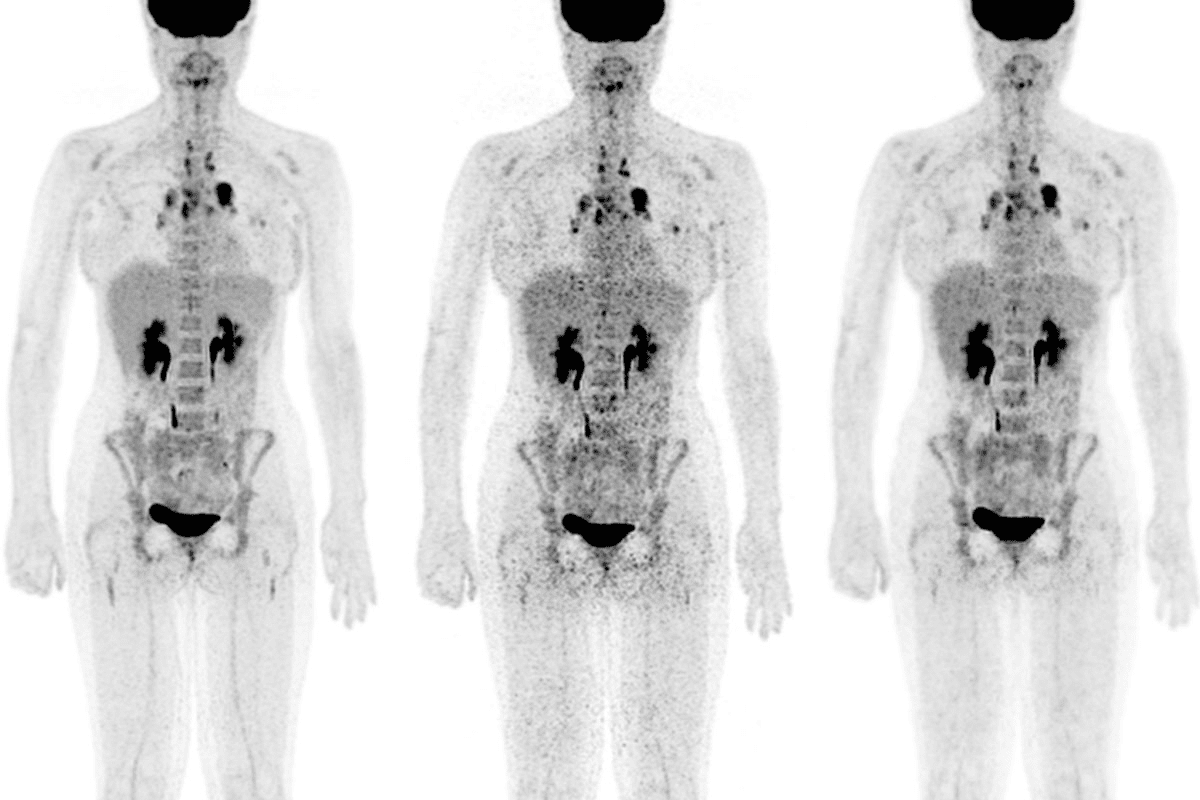

Hematological Symptoms of Beta Thalassemia Minor

Beta thalassemia minor is a mild form of thalassemia. It has distinct symptoms related to red blood cells. These symptoms are key for diagnosis and care.

Microcytic Anemia

Microcytic anemia is a main symptom of beta thalassemia minor. It means red blood cells are smaller than usual. This can cause fatigue and weakness because the blood can’t carry enough oxygen.

Reduced Hemoglobin Levels

People with beta thalassemia minor often have reduced hemoglobin levels. This can lead to symptoms like shortness of breath and pale skin. The low hemoglobin levels are due to the body’s trouble making beta-globin chains of hemoglobin.

Abnormal Red Blood Cell Morphology

Another key symptom is abnormal red blood cell morphology. The red blood cells are not only small but also have odd shapes. This can make it hard for them to move through blood vessels, leading to complications.

Knowing these symptoms is vital for diagnosing and managing beta thalassemia minor. By spotting signs of microcytic anemia, low hemoglobin, and odd red blood cell shapes, doctors can help those with the condition.

Diagnosing Beta Thalassemia Minor

To find out if someone has beta thalassemia minor, doctors use different tools. This process helps tell beta thalassemia minor apart from other types of anemia and thalassemia.

Blood Count Analysis

A Complete Blood Count (CBC) is often the first test for beta thalassemia minor. It checks the blood for:

- Red Blood Cell (RBC) count

- Hemoglobin levels

- Hematocrit

- Red Blood Cell indices (MCV, MCH, MCHC)

People with beta thalassemia minor usually have microcytic anemia. This means their red blood cells are smaller than usual.

Hemoglobin Electrophoresis

Hemoglobin electrophoresis is a key test for beta thalassemia minor. It looks at the different types of hemoglobin in the blood, like:

- Hemoglobin A (HbA)

- Hemoglobin A2 (HbA2)

- Hemoglobin F (HbF)

In beta thalassemia minor, there’s usually more Hemoglobin A2.